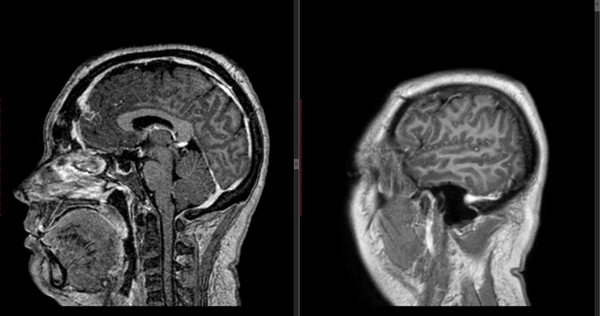

En RM de cerebro se observa lesión espacio ocupante selar-supraselar con aspecto multilobulado que invade cisterna interpeduncular y desplaza estructuras del tercer ventrículo. La misma es hiperintensa espontáneamente en T1 con captación heterogénea de contraste, hiperintensa en T2 (Figura 1). En secuencia de angioresonancia se observa su relación medial respecto a arterias carótidas no comprometiendo las mismas (Figura 2). A partir de éstas imágenes obtenidas en resonador 3 Tesla, en el Departamento de Innovación Tecnológica del Instituto Cardiológico de la Ciudad de Corrientes se realizó un proceso de segmentación de las distintas partes de interés (tumor, arterias, nervios ópticos y globos oculares). Para esto se utilizó el software “Open Source 3D Slicer (versión 4.11)” (Figura 3). Una vez segmentadas las regiones de interés, se realizó, mediante una impresora 3D “MAX” de la empresa Creatbot, un modelo 3D cuyos materiales consistieron en poliácido láctico (PLA) y poliuretano termoplástico (Figuras 4 y 5). Con el mismo, se realizó la planificación del abordaje quirúrgico.

Figura 1: RM en secuencia T1 cortes a) 1axial, se observa lesión espontáneamente hiperintensa y su relación con vasos del polígono de Willis. b) RM en secuencia T1 corte sagital, donde se observa extensión supraselar de la lesión comprimiendo lamina terminalis